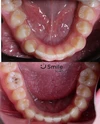

Diş Çapraşıklığı

Zirkonyum uygulamalar

Porselen uygulamaları

Laminate veneer